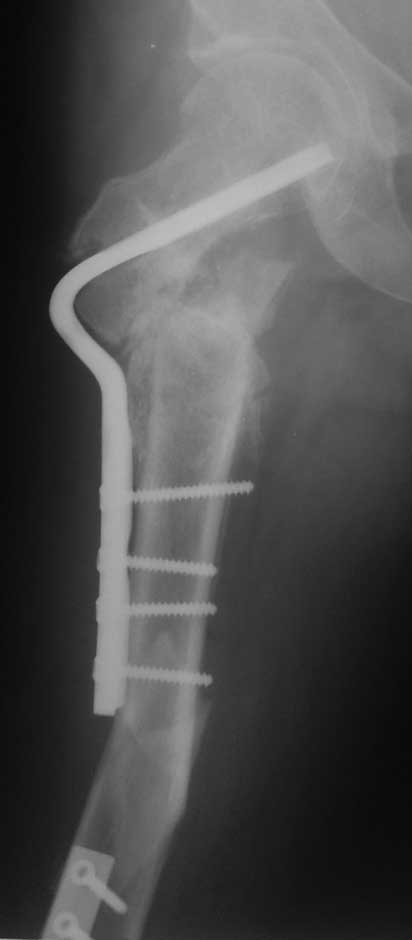

Уважаемые коллеги, помогите пожалуйста с тактикой лечения. Больная 43 лет, подвернув правую ногу, получила простой (А2) перелом правого бедра в с\3, м\у установленными ранее пластинами. В течении 4 недель лечится методом скелетного вытяжения.В анамнезе: в июне 2011г. получила перелом наружного мыщелка правого бедра на фоне консолидированного в порочном варусном положении перелома вертельной зоны (со слов травма 5 лет назад - лечилась консервативно), сопровождающимся укорочением 5 см. В одну операционную сессию выполнен остеосинтез перелома мыщелка бедра Т-образной пластиной и с целью коррекции укорочения выполнена вальгизирующая межвертельная остеотомия с фиксацией клинковой пластиной.На наш взгляд, наиболее простым является накостный остеосинтез диафизарного перелома по передней поверхности бедра, но смущает необходимость образования в последующем дополнительного кожного рубца. Пожалуйста, может быть у Вас есть другие мнения. Зарание благодарен. С уважением А.Гринь. ОКБ №2 г.Тюмень.

На снимке положение клинка идеальное, но шейка в ротации. Из-за неправильного расчета остеотомии не удалось латерализовать диафиз, и конечность находится в чрезмерном вальгусе. При укорочении с вальгусом увеличивает стресс в зоне между пластинами, и конструкция не выдерживает, и при малой травме может осложниться стрессовым переломом.

При правильной установке клинковая пластина без потери стабильности выдерживает вес пациента. Но здесь получился порочный круг, перелом мыщелка не позволяет нагружать, а без компрессии в зоне остеотомии нельзя добиться сращения. Пластина в данном случае работает как обычный нейтрализатор, хотя должна работать в динамическом режиме. Погоня за двумя зайцами не всегда верный способ, и можно было бы подождать с реконструкцией!

Из возможных операций: я бы предложил провести ретроградную фиксацию бедра после удаления дистальной пластины. При отсутствии полного сращения перелома можно установить пару шурупов спереди и сзади гвоздя, или можно оставить укороченный вариант пластины.

Гвоздь подвести под вертел, и оставить проксимальный винт, а остальные шурупы могут быть через один кортекс. Идеально установить "стоппер", который укоротит клинок и латерализует диафиз. Создаст компрессию!

Из бокового "субвастусного" доступа можно уложить пластину спереди, но тогда надо подождать с нагрузкой. Провокационный антеградный вариант технически сложен, но тогда теряется преимущества сколжения клинка в шейке, и потом клинок не разрушает, как остальные дивайсы, костную структуру в головке.